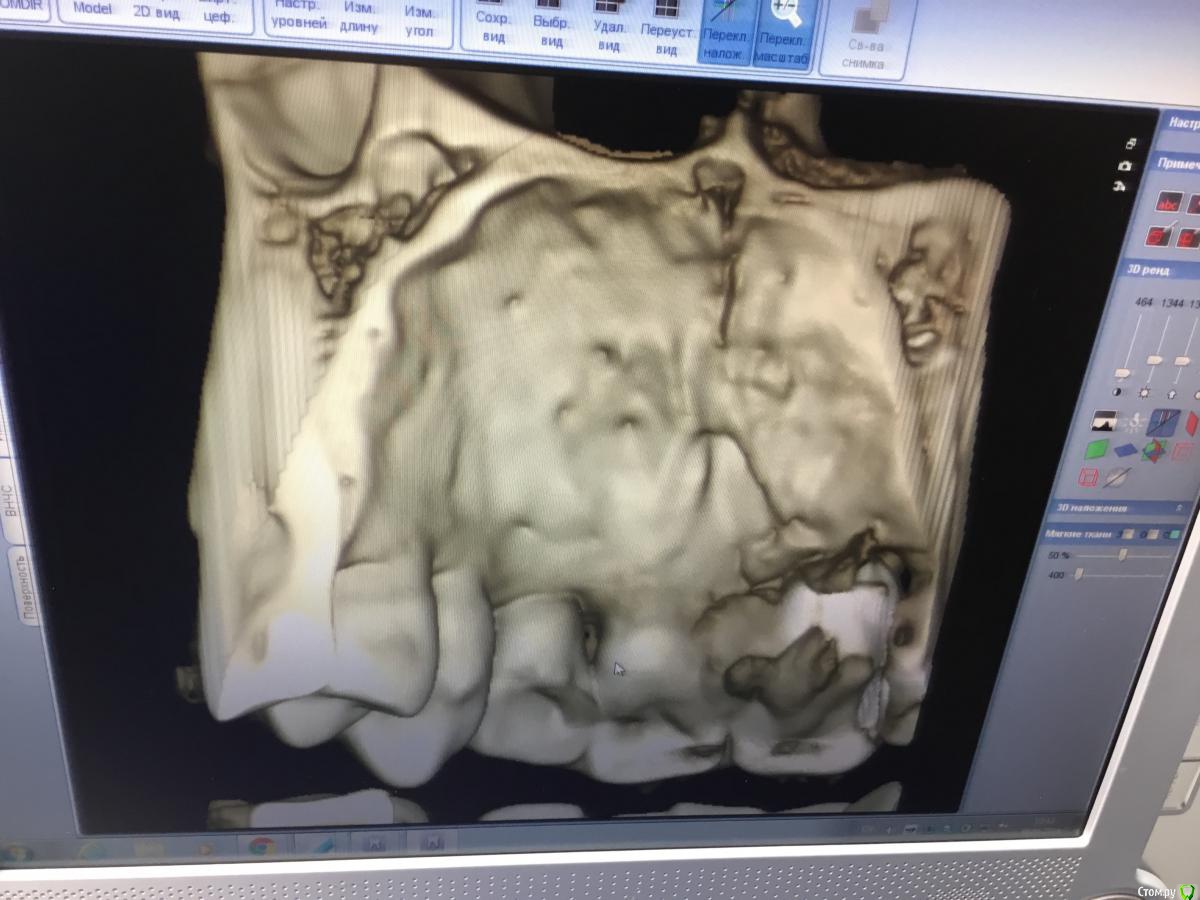

Zorrro Опубликовано 6 марта, 2016 Поделиться Опубликовано 6 марта, 2016 (изменено) Мой постоянный пациент привёл своего сынишку с жалобами на свищь на нёбе.Сделали кт и решили ,что вначале переберём каналы,а через пол года будем посмотреть куда нам двигаться дальше… Эстетика коронки на 11 вполне устраивала пациента,тем более он был уверен,что поставилимплант и вследствии коронку популярный доктор используя новейшие технологии и материалы,позволяющие не прибегать к устаревшим костным и ещё каким-то пластикам.запись к доктору уходила на пол года вперёд и молодой человек чудом втиснулся в этот плотный график,чтобы отхватить немножко и себе этих самых "новейших" технологий под нос. Фото ещё раз показывает,чтосамое главное в успехе частной практики это ВЕРА доктора в себя и то,что он делает.меня же коронка устраивала тем более,потому что переделывать её вместе с имплантом мне крайне не хотелось.обошлись комментарием про усиленную гигиену и регулярные наблюдения раз в пол года. итак занялись посильным трудом:отмыли 21 и 22,констрикция убежала за 50.02,остановились на 70.02 стальными файлами отступя 1мм,метапекс,через 2 недели irm и стекловолокно нафуджи+,филтек.договорились про контроль через пол года и коронки если всё ок. Ещё немного срезов до и преимущество кт перед прицельными снимкамиИ сразу после. Про коронки и корневой герметизм пациент не понял и решил оставить бломбы на месте. Изменено 6 марта, 2016 пользователем Zorrro 1 Ссылка на комментарий